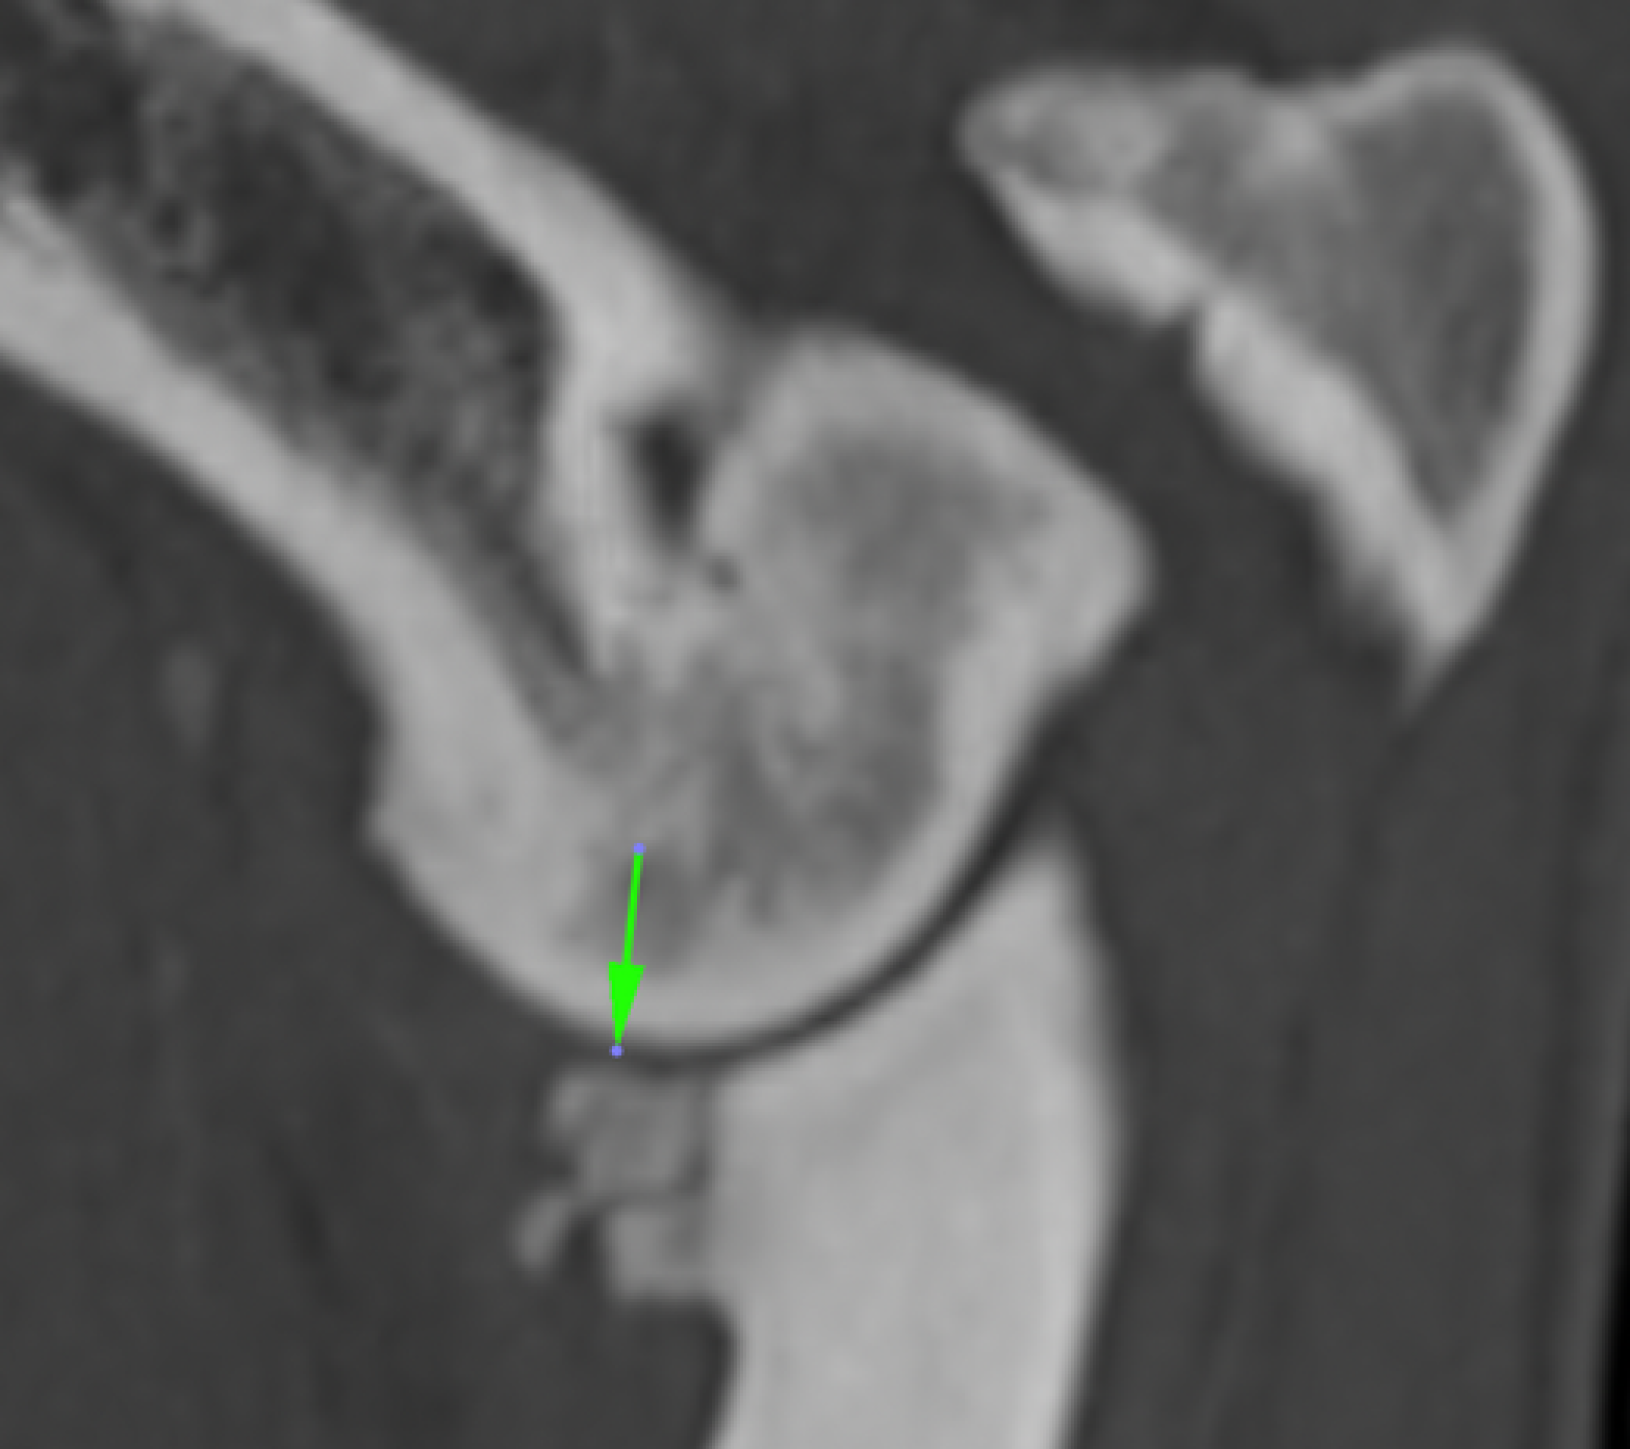

La Tomografía computerizada (CT) o TAC es la técnica por imagen de elección. El procesado avanzado de la imagen nos permitirá visualizar finos cortes de la anatomía y detectar pequeñas lesiones (por ejemplo, fragmentación del proceso coronoides), las cuales son difíciles de diagnosticar en radiografías convencionales.

• Enfermedad del proceso coronoides medial (EPCM): se trata de la condición más encontrada de todas las que se incluyen en la displasia de codo. El proceso coronoides puede encontrarse malformado, fisurado e incluso fragmentado. Como resultado de esta enfermedad y del roce anormal de dicha estructura con la superficie articular del cóndilo humeral medial, se produce un desgaste acelerado de las superficies cartilaginosas del aspecto medial del codo dando lugar al Síndrome del compartimento medial, el cual se ve favorecido por la sobrecarga que soporta la región interna de la articulación en condiciones fisiológicas.